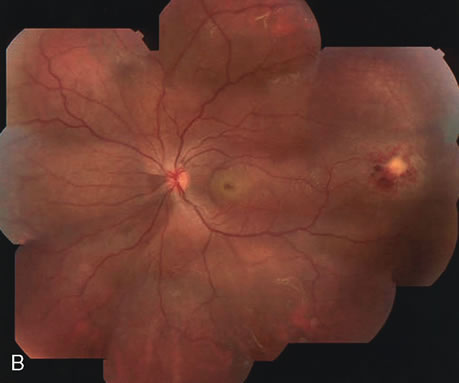

Clinically discernible peripheral dependent bullous neurosensory detachments have been described in patients with chronic CSC.85–92 Yannuzzi and co-workers first characterized the presence of RPE atrophic tracts extending inferiorly in the fundus periphery secondary to antecedent retinal detachment in patients with CSC.85 Presumably, there is a particularly severe and/or longstanding leakage of fluid from an RPE defect in the subretinal space at the posterior pole. The subretinal fluid gravitates inferiorly to form a dependent neurosensory detachment in a “flask,” “teardrop,” “dumbbell,” or “hourglass” pattern (Fig. 31). Sometimes the tract of subretinal fluid connecting the macular detachment with the bullous neurosensory detachment in the inferior hemisphere is so shallow that it is very difficult to appreciate. The RPE under the chronic retinal detachment experiences atrophic changes that appear as atrophic RPE tracts connecting the posterior pole with the dependent retinal detachment. The retina itself develops secondary manifestations including pigment migration, capillary dilatation (telangiectasia) proximally and capillary nonperfusion (ischemia) distally to the area of detached retina (see Fig. 31). The changes in the RPE consist of both RPE atrophy and pigment clumping in the form of perivascular deposits or bone spicules, a condition described by Gass as a “pseudoretinitis pigmentosa–like atypical CSC presentation.”87

Other complications noted in these patients are cystoid macular edema or, more frequently, cystoid retinal changes in the areas of chronic detachment, subretinal lipid deposition, choriocapillaris atrophy secondary to the RPE damage in the areas of RPE tracts, and CNV.89,90,204–206 This severe variant of CSC appears to be more frequent in patients of Latin or Asian ancestry, and it is usually associated with frequent recurrences, permanent central vision loss, and significant superior visual field loss. |